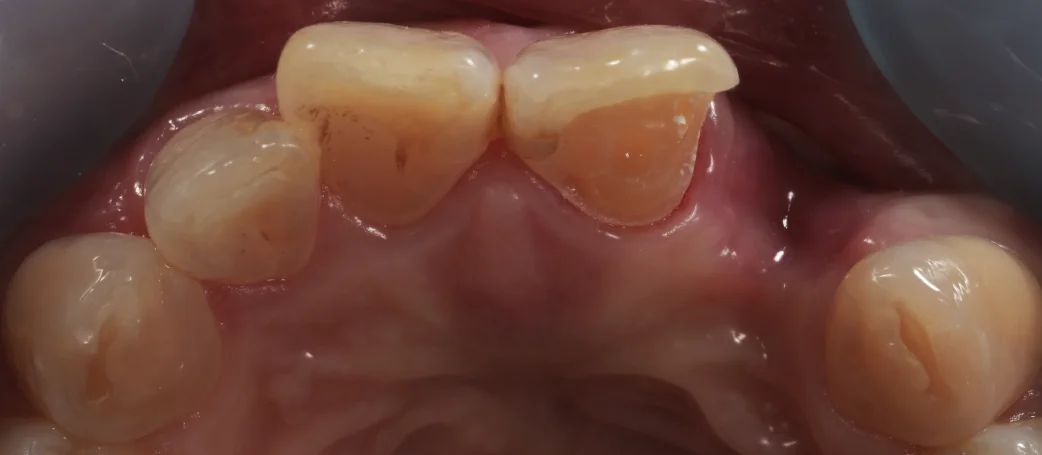

噛む面からの写真がこちらになります。

ちょっと暗いのでわかりづらいですが・・・

画面中央の2本の歯のうち、左側の歯の内側のごく一部だけを一層削っています。

最終的なものを入れた状態の写真がこちらです。

こんな感じで、一層削った部分だけを覆って、横に伸ばしているんですね。

こう言った治療法を「シングルリテーナー接着ブリッジ」といいます。

要は接着ブリッジのメタルフリー版って感じをイメージして貰えばわかりやすいですね。